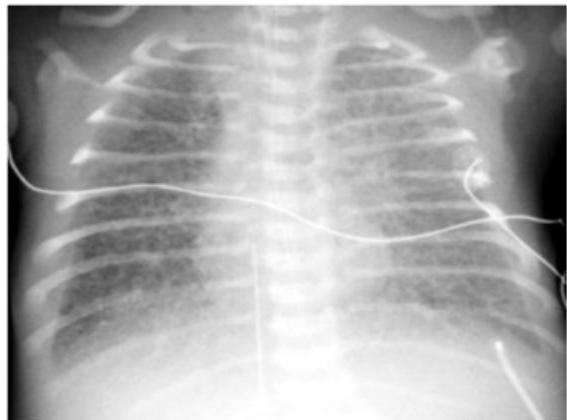

Preterm Infant with Respiratory Distress

- Preterm 29 weeks gestation C/S delivery showed severe respiratory distress soon after birth - RDS

- Air bronchograms

-

There is a homogeneous opacification of both lungs with white-out lungs - (1 .field (grounds glass appearance) and air bronchogram bilaterally

.The diagnosis is Acute Respiratory Distress Syndrome (ARDS) - (2

- .I- Massive blood transfusions Preterm 29-weeks gestation C/S delivery showed severe respiratory distress soon after birth. This chest x-ray was taken at the age of 6 hours.

- Q1: Write 2 abnormalities in the X-Ray?

- Q2: What is the likely diagnosis?

- Q3: Write 2 management steps.

Answers:

- Q1: Ground glass appearance, wide intercostal space.

- Q3: Mechanical ventilation, give Surfactant for lungs maturation.

Respiratory Distress Syndrome (Premature Neonate)

X-ray? Ground glass appearance of the lungs with air bronchogram.

Diagnosis? Respiratory Distress Syndrome.